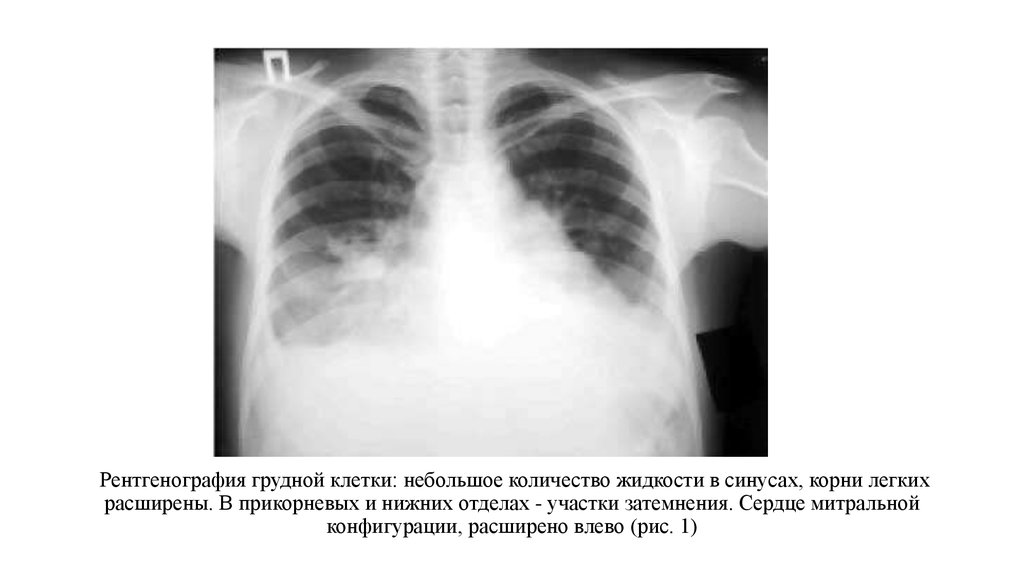

Симптомы и причины скопления воды в легких